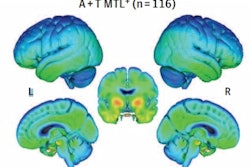

Associations of baseline beta-amyloid PET and baseline phosphorylated tau-181 (p-tau181) with F-18 flortaucipir (FTP) Standardized uptake value ratio (SUVR) annualized change for (A) cognitively unimpaired and (B) cognitively impaired individuals. Brain surface renderings depict Pearson correlation coefficients adjusted for age and sex (r) representing the strength of the association between the different biomarkers and F-18 flortaucipir SUVR change in each brain region. The right upper panel represents age- and sex-adjusted Pearson correlation coefficients (r), along with p-values, for the association between the biomarkers and F-18 flortaucipir SUVR change in the Alzheimer's disease meta-region of interest (ROI). The root mean squared error (RMSE) for the prediction of F-18 flortaucipir SUVR change by a linear model with the biomarker as predictor and age and sex as covariates. RMSE was estimated using leave-one-out cross-validation. Voxel-wise statistical maps were thresholded using more lenient cluster-forming thresholds of p < 0.05 (uncorrected) at the voxel level and further thresholded at the cluster level by restricting results to clusters with a number of voxels higher than the expected number of voxels as predicted using random field theory. Image courtesy of Alzheimer's & Dementia: The Journal of the Alzheimer's Association.